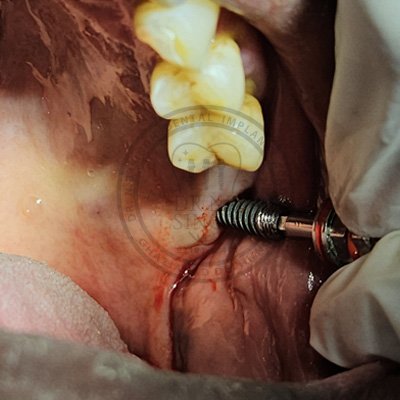

Case – 11 Baleram